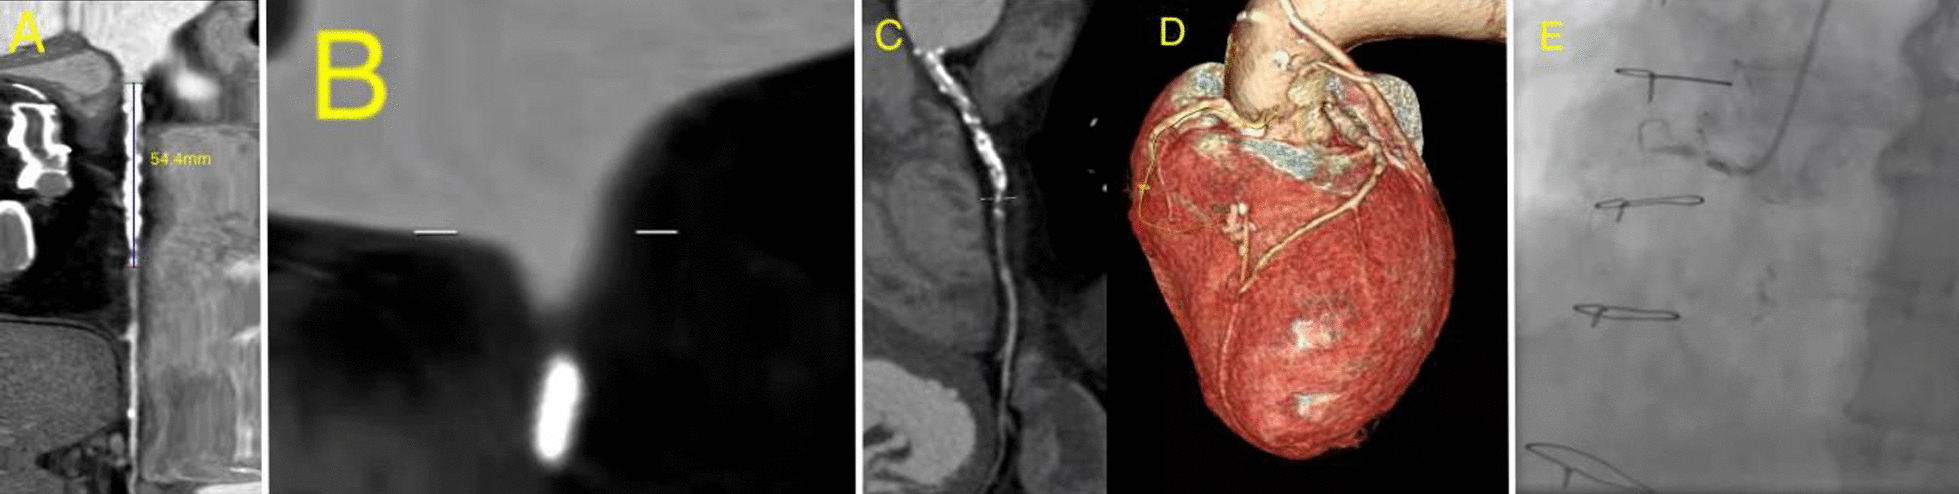

Fig. 2.

A CTO lesion in the proximal segment of RCA: with CABG history, age 77, Length > 20 mm, blunt stump, severe calcification, non-severely tortuosity. A–D The CASTLECTA score was 5. E CASTLECAG score was 4